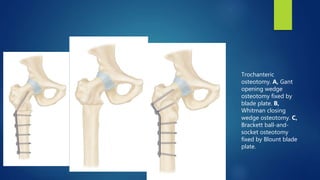

Trochanteric

osteotomy. A, Gant

opening wedge

osteotomy fixed by

blade plate. B,

Whitman closing

wedge osteotomy. C,

Brackett ball-and-

socket osteotomy

fixed by Blount blade

plate.

Trochanteric osteotomy. A, Gant openingwedge osteotomy fixed by blade plate. B, Whitman closing wedge osteotomy. C, Brackett ball-and- socket osteotomy fixed by Blount blade plate.